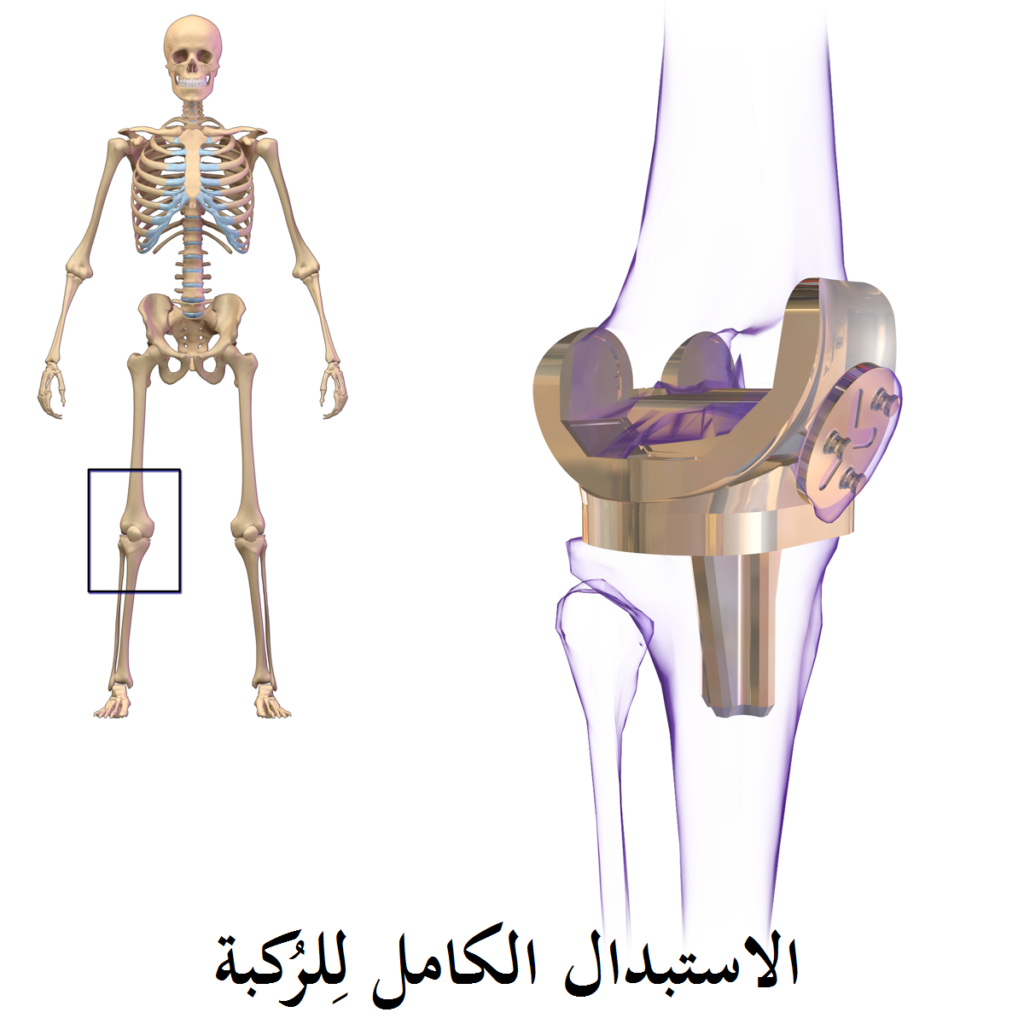

افضل انواع المفاصل الصناعية للركبة

استخدام مفصل بديل للمفصل الطبيعي للركبة يمكنك من ممارسة وظائفك الحيوية مرة أخرى، ولكن ماهو النوع المناسب لك، وماهي الأنواع المتوفرة والفرق بينهم.

يمكننا التعرف على انواع مفصل الركبة واسعارها في النقاط التالية:

هذا النوع من الأعضاء البديلة هو أكثر طرف بديل للركبة شيوعاً ويستبدل مفصل الركبة بشكل كامل: يتم استبدال سطوح المفصل الخاصة بعظم الفخذ وعظم الظنبوب وأحيانا الرضفة المهم في هذا السياق أن تكون أربطة الركبة المثبتة للمحور كالرباط الخارجي والداخلي محافظ عليها و فعالة بهذا يمكن للمرء أن يزرع هذا العضو البديل حتى لو كان الرباط الصليبي الأمامي مدمر الأربطة الخارجية والداخلية تساهم بشكل حاسم في توازن الركبة حينما يكونان الرباط الصليبي الأمامي والخلفي غير ثابتين يمكن زراعة عضو بديل خلفي مثبِّت هذا العضو يتبنى وظائف الرباط الصليبي من خلال تحويل ضغط الفخذ للخلف والظنبوب للأمام عمليات الركبة الصناعية.

الهدف من عملية استبدال مفصل الركبة هو علاج تآكل الغضروف في مفصل الركبة، الذي يحدث غالباً نتيجة لالتهاب المفاصل المزمن على إختلاف أنواعه، و يتم اٍجراء عملية استبدال مفصل الركبة تحت تأثير التخدير العام أو الموضعي، ولكم كم سعر مفصل الركبة الصناعي هذا ما سنتعرف عليه بالتفصيل هنا:

تكلفة عمليات تغيير مفصل الركبة:15.500 €